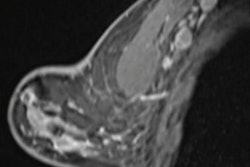

Alpinion's new X-Cube 90 premium ultrasound system. Image courtesy of Alpinion.X-Cube 90, which will serve as the flagship offering in the firm's X-Cube ultrasound product line, features Alpinion's X+ Architecture, an imaging platform that combines Alpinion's X+ Crystal signature transducer technology with its X+ Fit beamforming and data processing techniques, according to Alpinion.